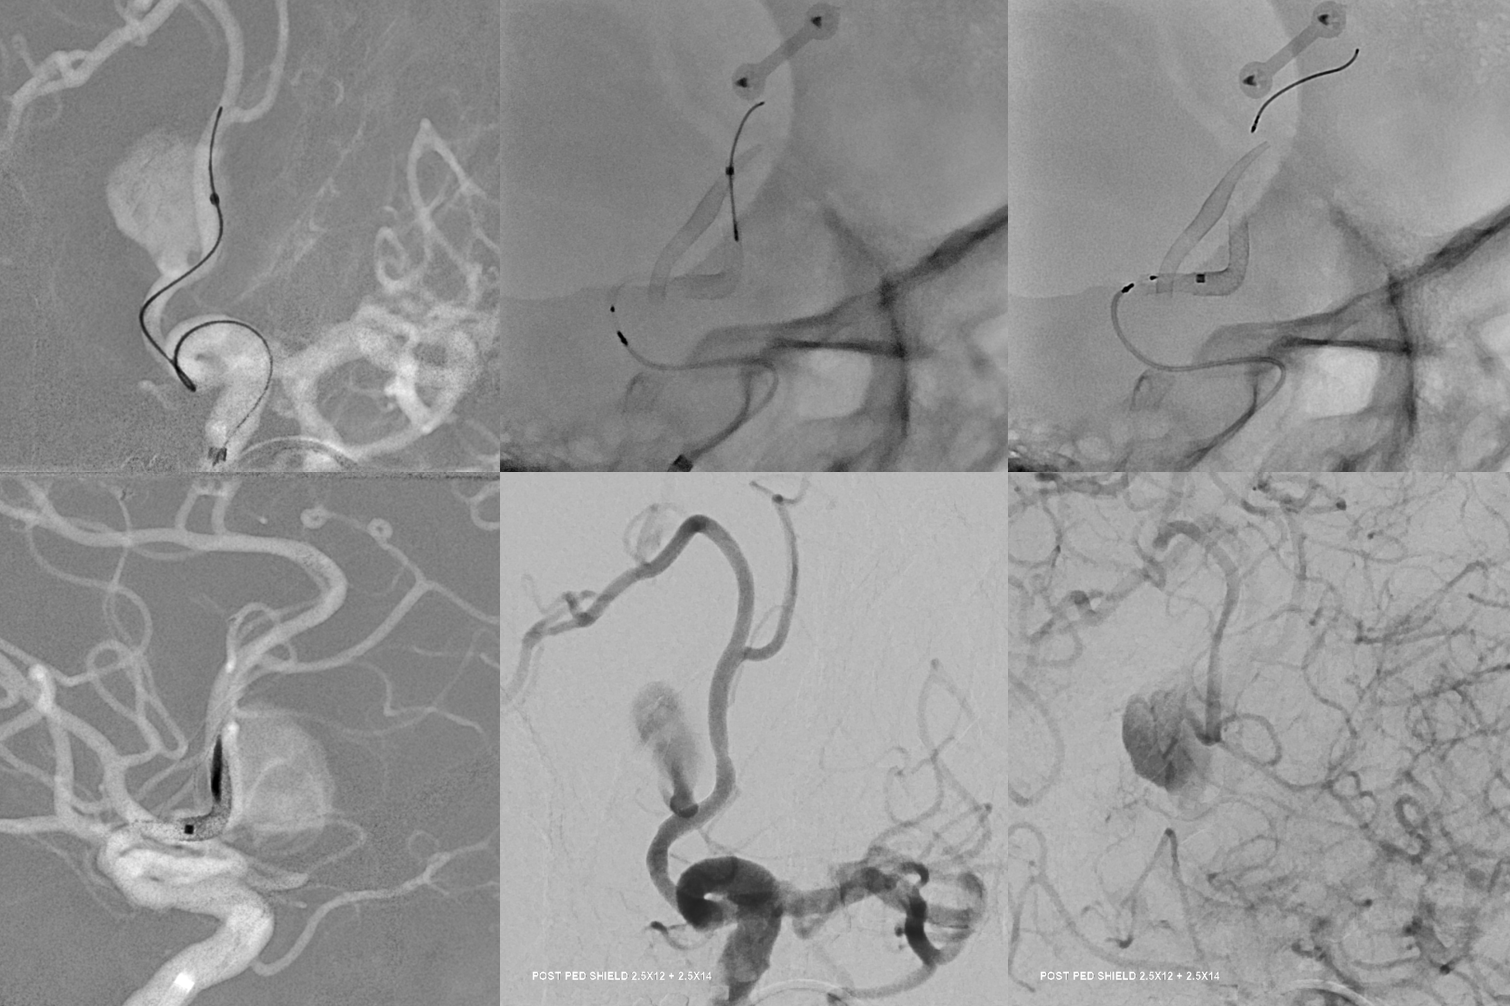

Can we sac the ACOM now? Coil aneurysm and the ACOM? Why not? Can argue for that. We choose H-Flow Diversion. A1-A2 bilaterally. On the right, we have to access the A1-A2 via the PCOM. This is not a job for 27 or 21 catheter. Plan for Silk Vista Baby on right and Pipeline Shield on left

Aristotle 14 soft and Scepter C 4×10

Now we do a BTO of the right A2. Its not a perfect occlusion there is a small endoleak. Still, the brisk filling of right A2 suggests what?

Two Pipe Shields are placed. This is how we work. This big one is not a job for one and done

Post. Bilateral injections. The right ACA is supplied retrogradely via the ACA-ACA bypass. The MOST important finding here is that there is no longer flow across the ACOM. This is what flow modification is. Changing dynamics to impact aneurysm.

Robust bypass supports superior division and some more

No aneurysm, as suspected

Stereo pairs

Bypasses. Note A3-A3 patent bypass, as well as STA-MCA. Both seen thru radiolucent skull windows